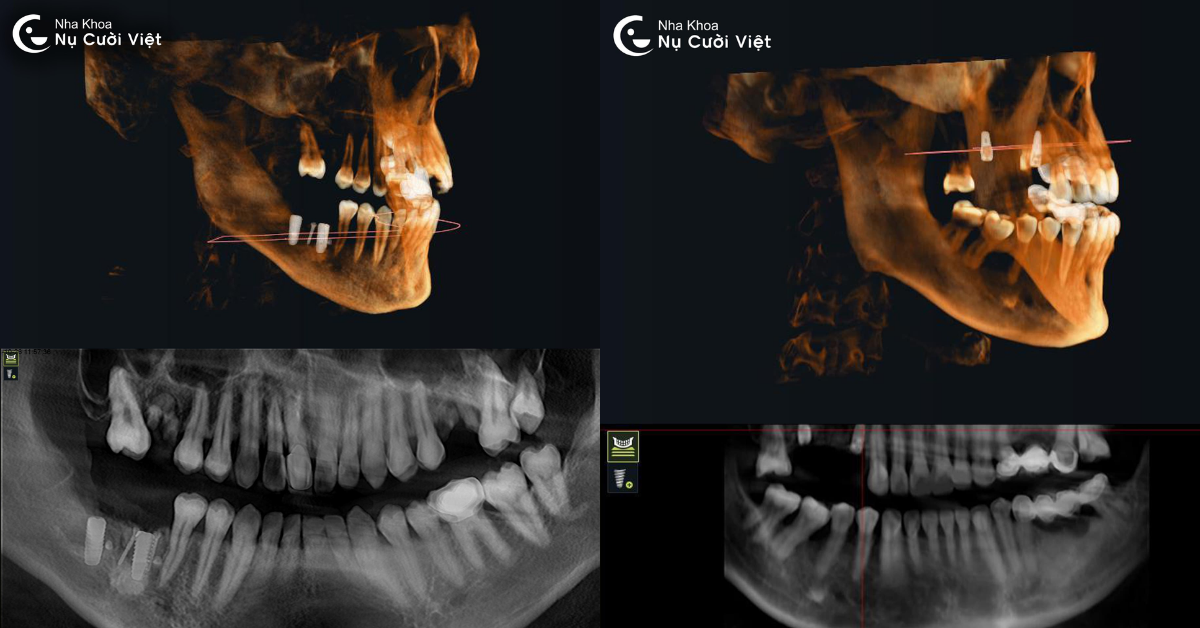

Kỹ thuật này sử dụng tia X hình nón để quét toàn bộ cấu trúc vùng hàm mặt và răng trong một lần chụp duy nhất. So với phim X-quang thông thường chỉ cho hình ảnh hai chiều (2D), ConeBeam CT cung cấp góc nhìn toàn cảnh ba chiều (3D) có độ phân giải cao, thể hiện chi tiết từng lát cắt của xương, mô mềm, ống thần kinh và xoang hàm. Khi thực hiện chụp, đầu máy sẽ xoay 360 độ quanh vùng hàm mặt trong vài giây để thu thập dữ liệu. Hệ thống cảm biến đặc biệt sẽ ghi lại hàng trăm lớp cắt siêu mỏng của vùng cần khảo sát.

Chỉ với một lần chụp duy nhất, bác sĩ có thể quan sát hàng triệu góc nhìn, từ trên xuống, từ dưới lên, mặt bên, mặt nghiêng… Từ đó dễ dàng phát hiện các vấn đề tiềm ẩn như tiêu xương, viêm quanh chân răng cũ, khoảng cách đến dây thần kinh, độ sâu xoang hàm… giúp quá trình lập kế hoạch trồng Implant trở nên chính xác và cá nhân hóa cho từng khách hàng.